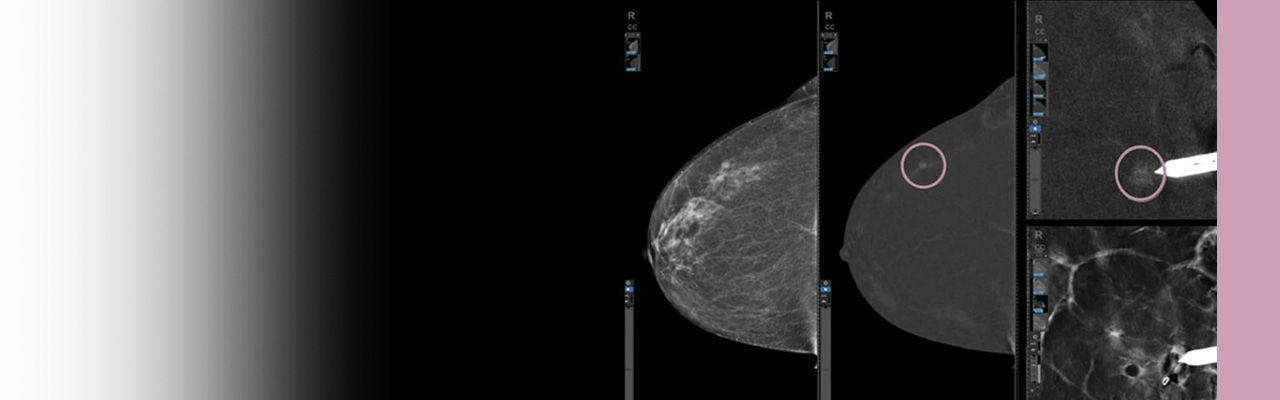

Customized image accessibility

eContrast post-processing offers four contrast levels for optimal diagnosis.